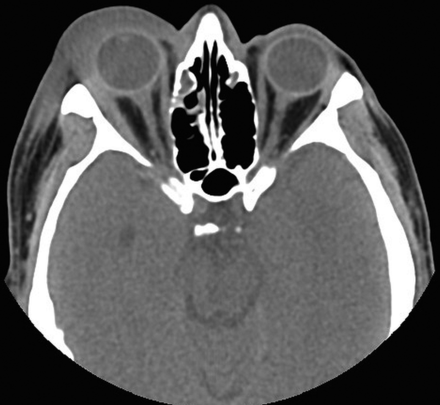

眼外肌ct图像,眼外肌六条肌解剖图

mr影像ct影像眼的附属结构:由眼外肌,视神经,泪器以及眶内的脂肪,血管

头部轴位 ct(未造影)示右侧外直肌及肌腱增厚.

分别为眼眶横断面脂肪抑制t1wi和t2wi,示两眼球突出,两侧多条眼外肌增